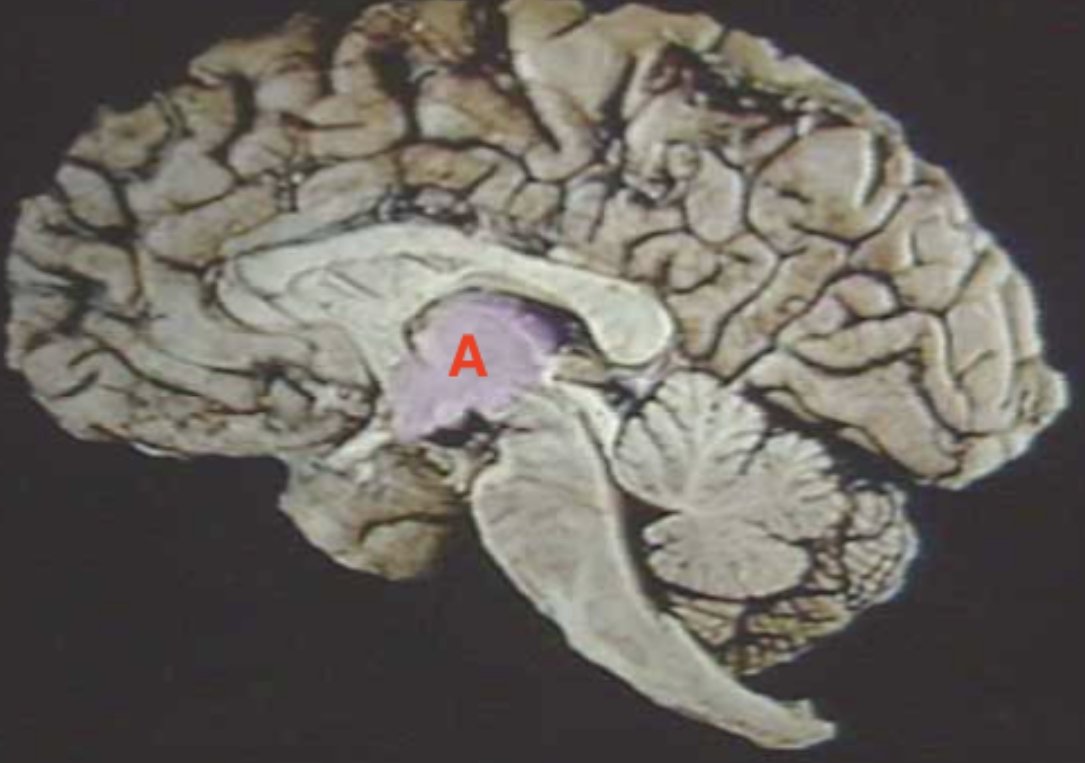

What is the arrow pointing at?

Amygdala